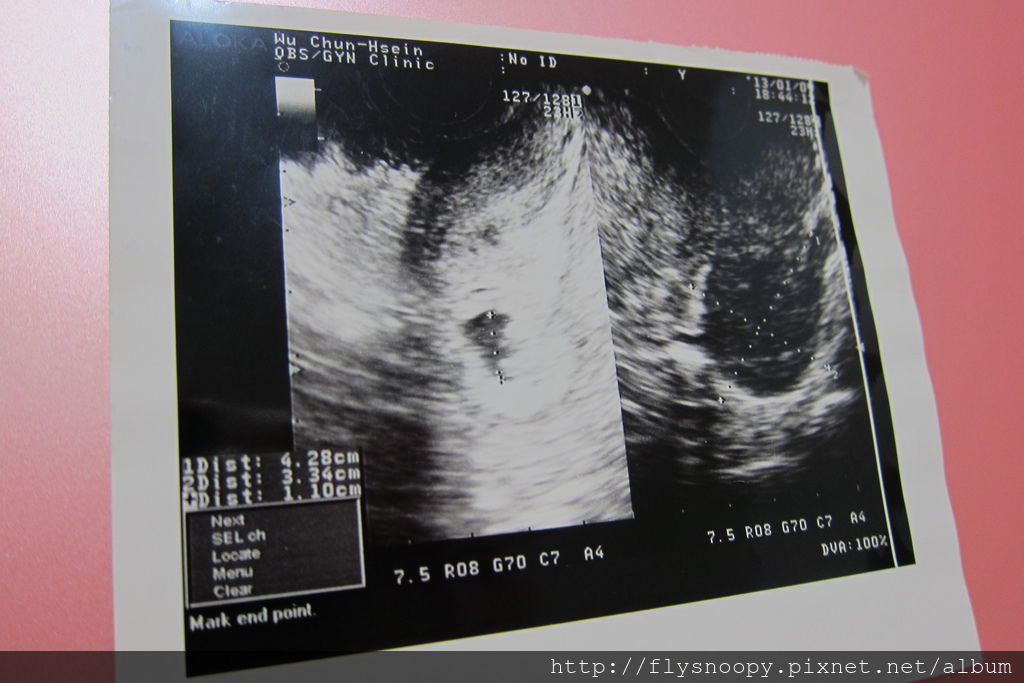

不過還要看是否胚囊是否有著床成功,醫生拿出一個圖片給我們看,

因為照超音波時還看不出來胚囊,但是有驗到兩條線,

接著就是要看胚囊有沒有成功在子宮著床,不然就變成子宮外孕了。

2013.1.7照到胚囊囉